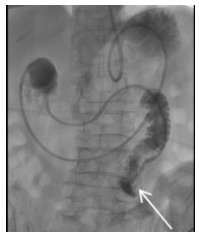

患者行支架植入后第二天即出现进食后呕吐,肠鸣音减弱,即便进流食同样呕吐。可能与覆膜支架阻碍了SMA近段空回肠动脉的血流导致胃肠动力障碍,胃潴留(图 6)。患者肠鸣音可闻及,有排气,推测未出现肠缺血坏死。为了增强营养支持治疗,给予患者经鼻腔植入空回肠营养管,并将其远端通过十二指肠送入空肠(图 7)。留置营养管出院,院外口服利伐沙班片25 mg 1次/d。1个月后患者循序渐进尝试经口进流食,未出现呕吐,遂拔除营养管,2个月后恢复普通饮食,随访至半年未再出现腹痛症状。

| 图 7 经鼻植入营养管,远端进入空肠(箭头示) |